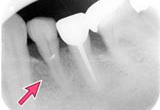

| 治療前 | 1年後 | 1年半後 | ||

![]() |